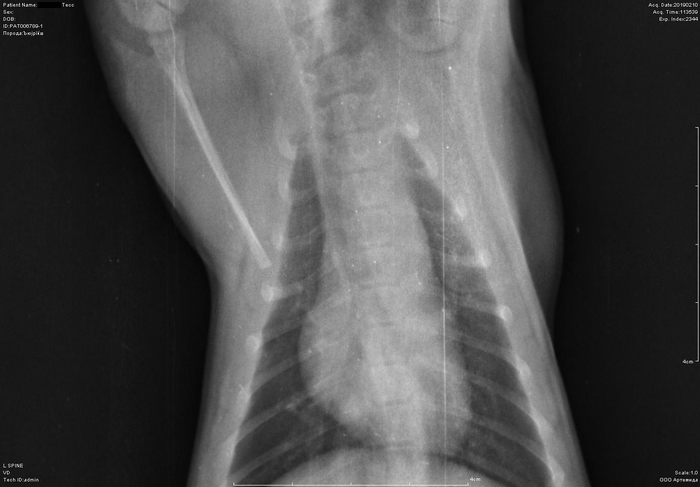

Рентген котенка

Добрый день. Котенок рожден 5 ноября 2018 года, девочка, не привита. Проглистована. Неожиданно в один момент стала припадать на задние ноги. Как бы бережет их и старается не прыгать лишний раз. Свозили два дня назад к ветеринару - всю её прощупал, говорит переломов нет, вывихов тоже. Сделали блокаду ближе в крестцу новокаина, чтобы снять симптомы. Прописал кальций в таблетках Ексел. Сейчас всё примерно так же - лапки задние бережет, но стала по активнее. Прошу специалистов, если такие тут бывают, оценить снимки, т.к. врач ещё кое-что сказал и хотелось бы услышать ваше мнение. Скан расшифровки и д/з потом приложу.

Боковая проекция